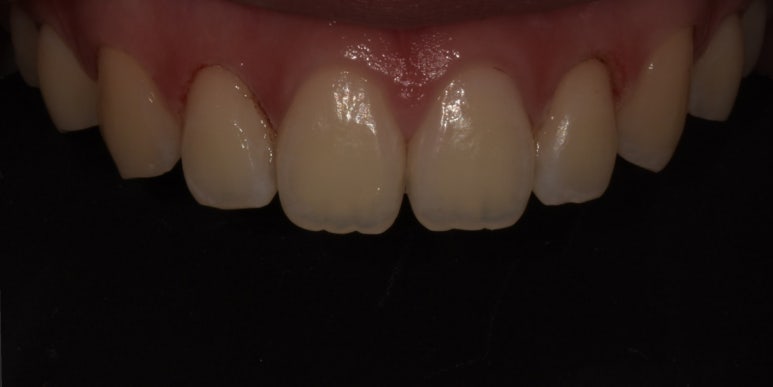

잇몸성형 전후 사진

(전) 2023-05-04 (후) 2023-05-17

위 환자분은 상악 측절치 #12, 22만 다른 치아보다 잇몸이 많이 내려와 있어 다른 치아와의 밸런스를 맞춰주었습니다.